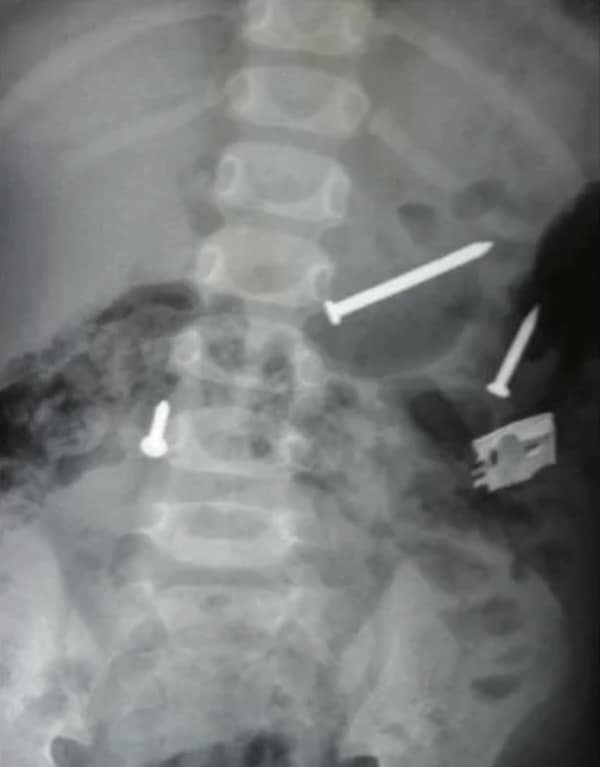

Weird xray photos

I used to think that nothing could surprise me anymore—until I stumbled upon some weird x-ray photos that made me reconsider my stance on human ingenuity (or lack thereof). Apparently, some people have a knack for getting objects lodged where they absolutely shouldn’t be. If you’ve ever wondered how not to use everyday items, these images might provide some unintended guidance.

This collection showcases 31 bizarre x-ray images that defy logic and anatomy textbooks alike. Each photo reveals unexpected objects making cameo appearances inside the human body, turning medical imaging into a gallery of the absurd. From common household items inexplicably found in unusual places to anomalies that would leave even seasoned doctors scratching their heads, these images offer a perplexing glimpse into the more “creative” side of medical emergencies. They highlight the intersection of curiosity, misadventure, and perhaps a dash of poor decision-making, all captured through the lens of radiology.